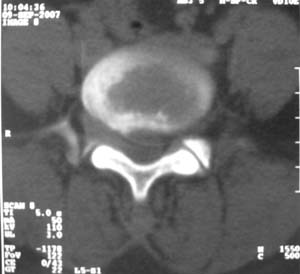

标题: CT9676:女,34岁,腰5骶1右侧神经根增粗?请各位老师会诊! [打印本页]

标题: CT9676:女,34岁,腰5骶1右侧神经根增粗?请各位老师会诊!

女,34岁,腰背部及右下肢酸痛两年余.

神经源性肿瘤可能性大;1椎间孔较对侧明显大,2相应层面似见椎间盘边缘.建议作mri.

神经源性肿瘤?突出?椎间盘扫描的层厚太厚了。建议mri或薄层扫描

对比观察

[emb10]为什么说是椎间盘病变呢?还有椎间盘脱出有脱向头端方向的吗?

腰间盘突出是有的,右侧椎间孔增大,还是做个mri吧。

右侧椎间孔显宽,考虑为体位不对称所致.扫描层厚偏厚了,考虑孔间型间盘突出.